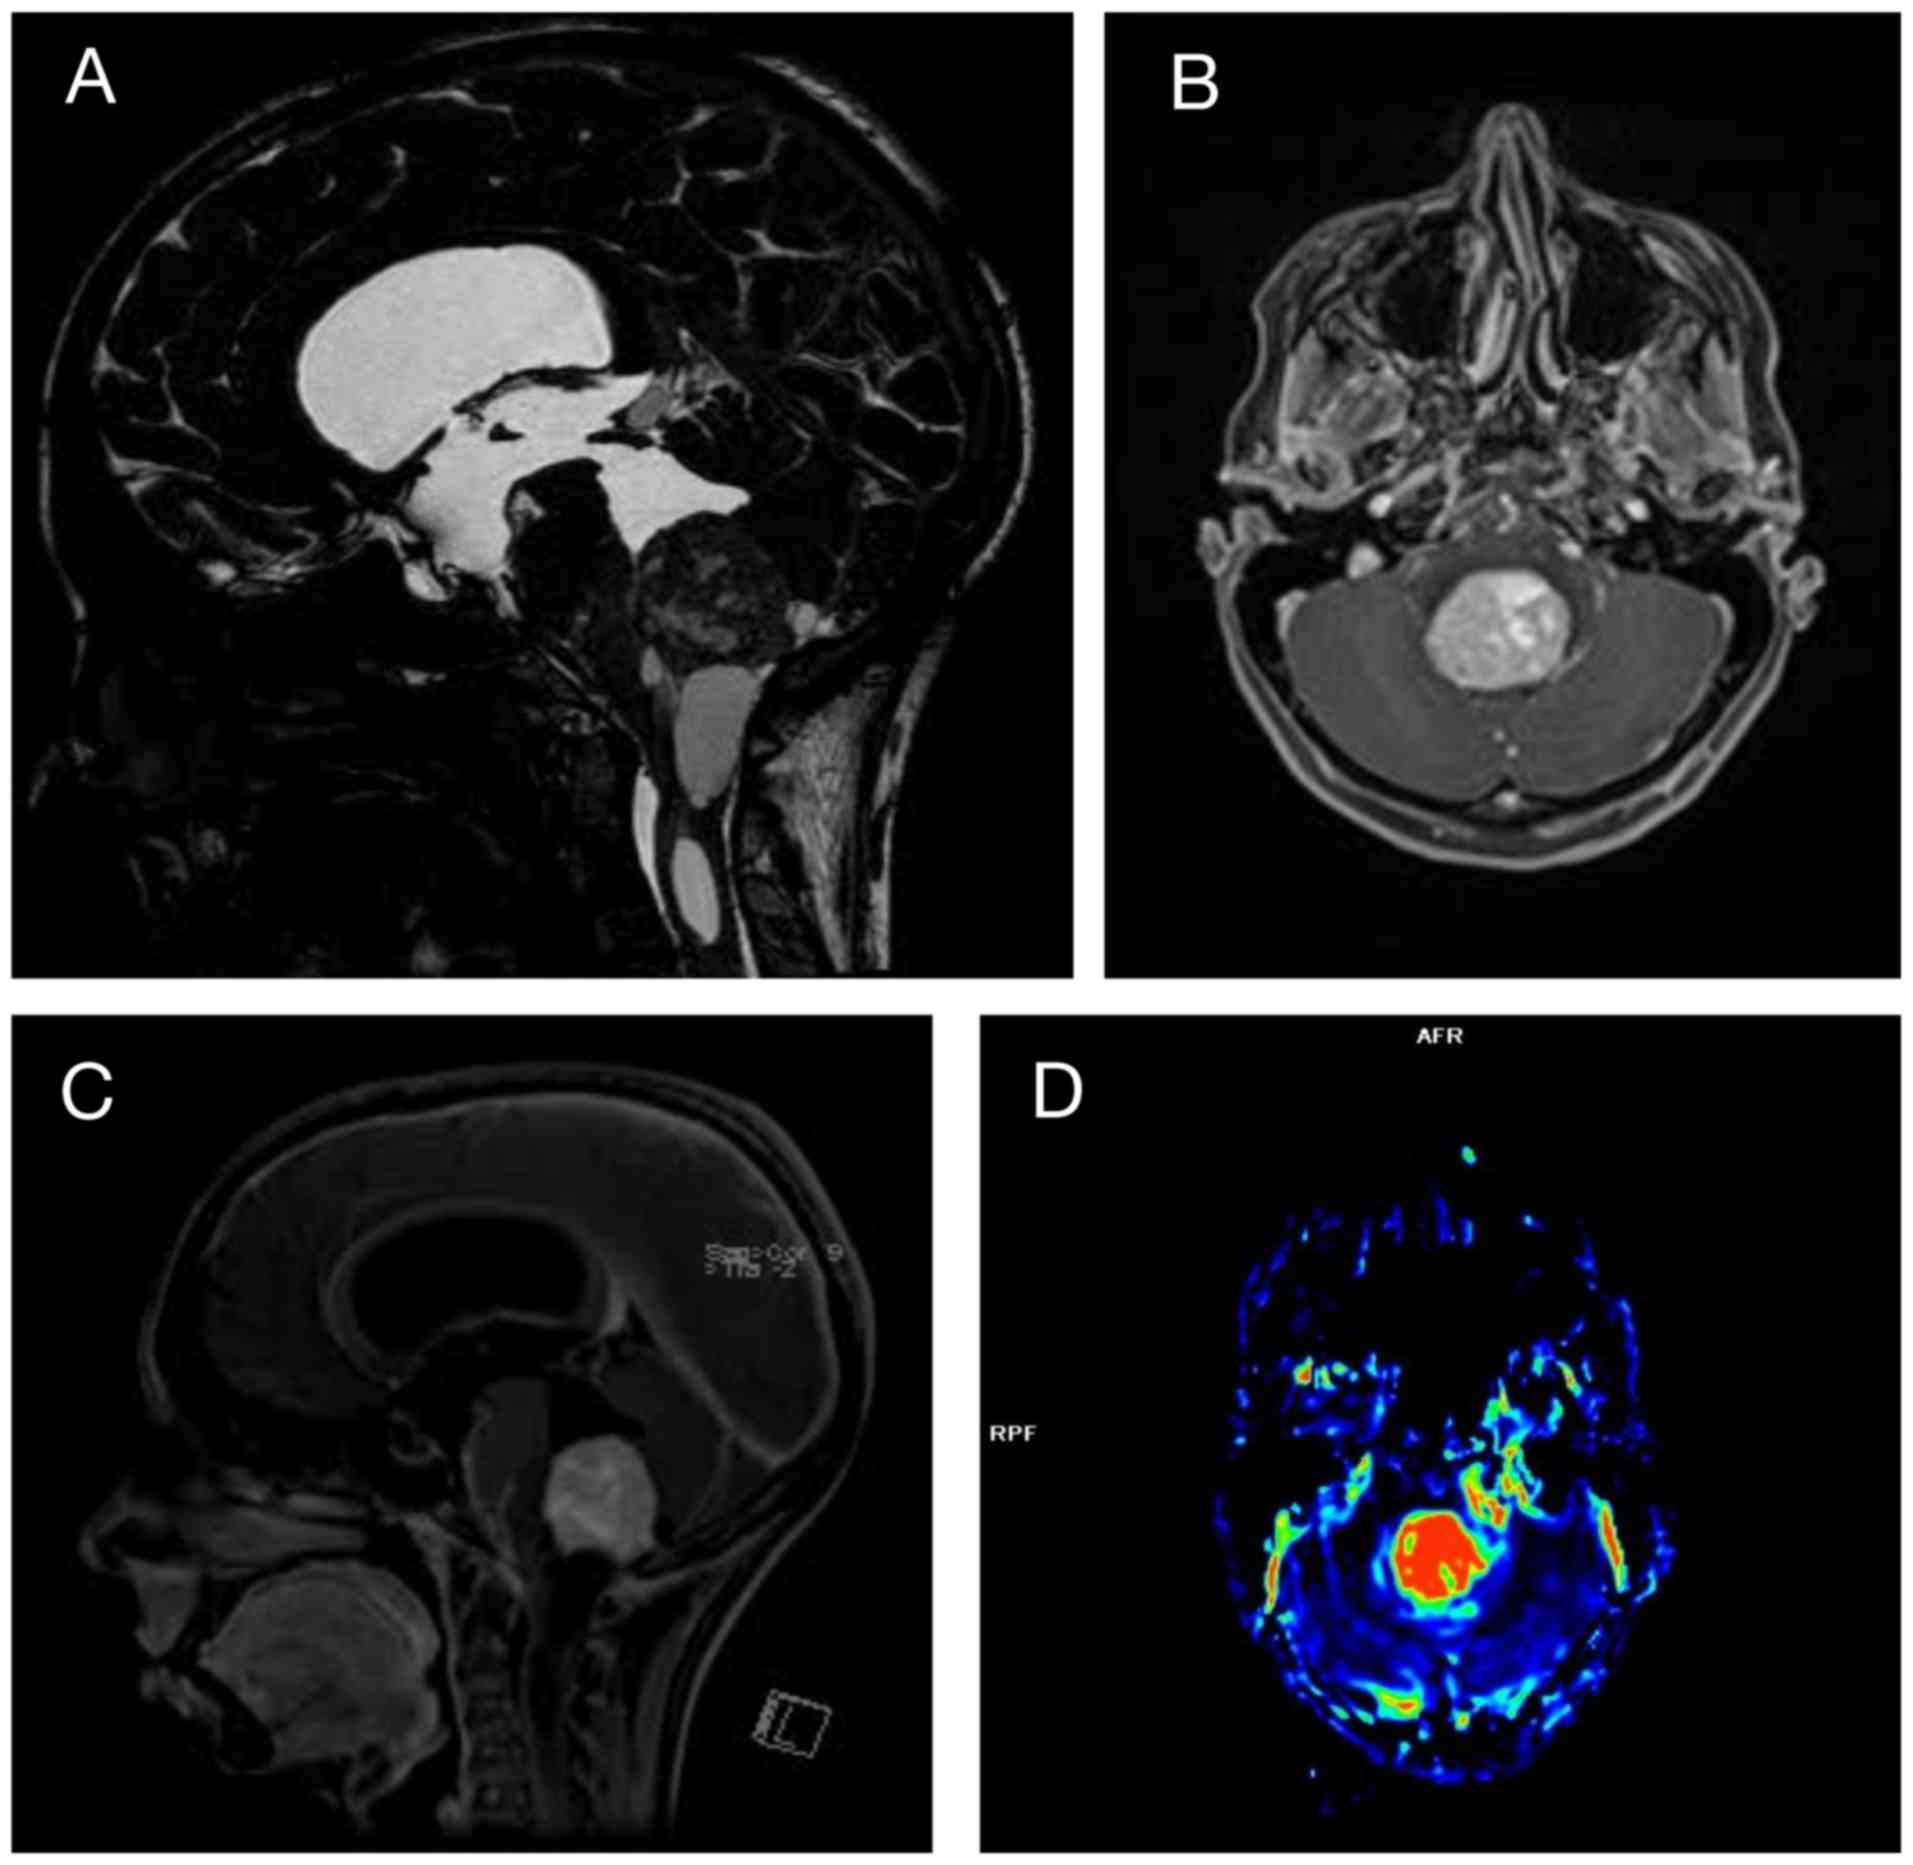

After 3 weeks of hospitalization, the patient

developed progressive gait abnormality, along with bilateral

dysmetria, which was worse on the left side. A brain magnetic

resonance imaging (MRI) examination revealed a massive lesion with

vascular characteristics suggestive of a HB in the fourth ventricle

causing hypertensive hydrocephalus (Fig. 1). This lesion, together with the

pancreatic cysts, supported the diagnosis of VHLs. Whole blood was

eliminated. Six months post-radiotherapy, an MRI examination

revealed no significant alterations in the size of the lesion.